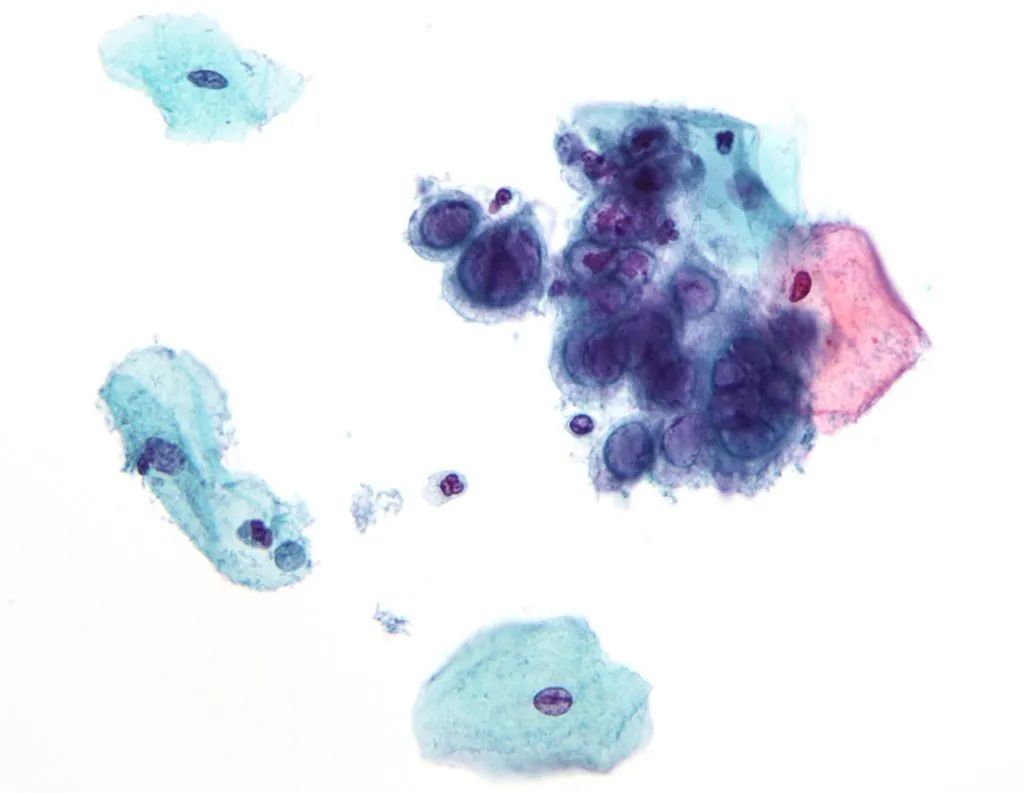

HSV-1感染的细胞(图源:wiki)

有趣的是,研究者观察到hiNSC一些特殊的变化。简单来说,被感染的hiNSC形成了特殊的多细胞结构,与此前研究发现的阿尔茨海默病患者大脑中的合胞体相似[5]。感染时神经元越不成熟,形成的多细胞团块结构就越大。

HSV-1感染导致的多细胞结构